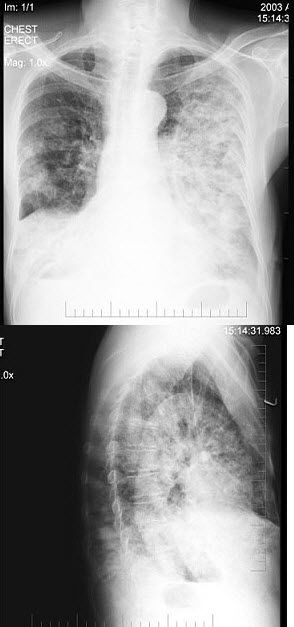

40、单项选择题

60岁,男,有长期抽烟史,左声带麻痹、声音嘶哑2个月,请结合胸片和CT图,选出最可能的诊断()

A.肺癌

B.肺结核

C.尘肺

D.肺炎

E.肺结节病